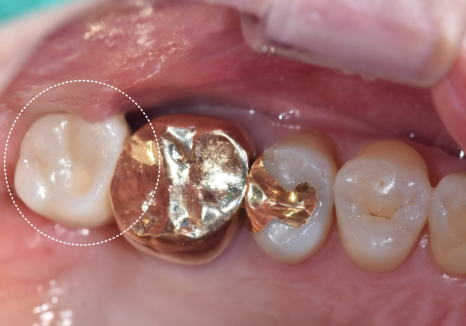

얼마 전 오른쪽 위 어금니가

심하게 흔들린다며 한 환자분이 내원하셨어요.

입안을 살펴보니 예전 금니 아래로

잇몸이 쑥 내려가 뿌리가 훤히 드러나 있었고,

잇몸은 이미 붉게 부어있는 상태였죠.

잇몸이 내려가다 보니 치아 사이 빈 공간으로

음식물이 가득 끼어있었는데,,

치아 사이는 칫솔이 잘 닿지 않아

남은 음식물이 잇몸을 더 빠르게 녹이고 있었습니다.